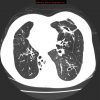

– Giãn phế quản (Bronchiectasis) là giãn không hồi phục một phần của cây phế quản và thường đi kèm với hiện tượng dày thành phế quản và ứ đọng chất nhầy. Có thể giãn ở phế quản lớn trong khi phế quản nhỏ vẫn bình thường hoặc giãn ở phế quản nhỏ trong khi phế quản lớn bình thường.

– Bình thường khẩu kính phế quản ngang với khẩu kính động mạch đi kèm. Trường hợp giãn phế quản, khẩu kính của phế quản sẽ lớn hơn động mạch đi kèm.

– Giãn dạng khu trú hay gặp nhất. Thường gặp ở các phân thùy đáy sau (50%), thùy giữa hoặc thùy lưỡi (10%)